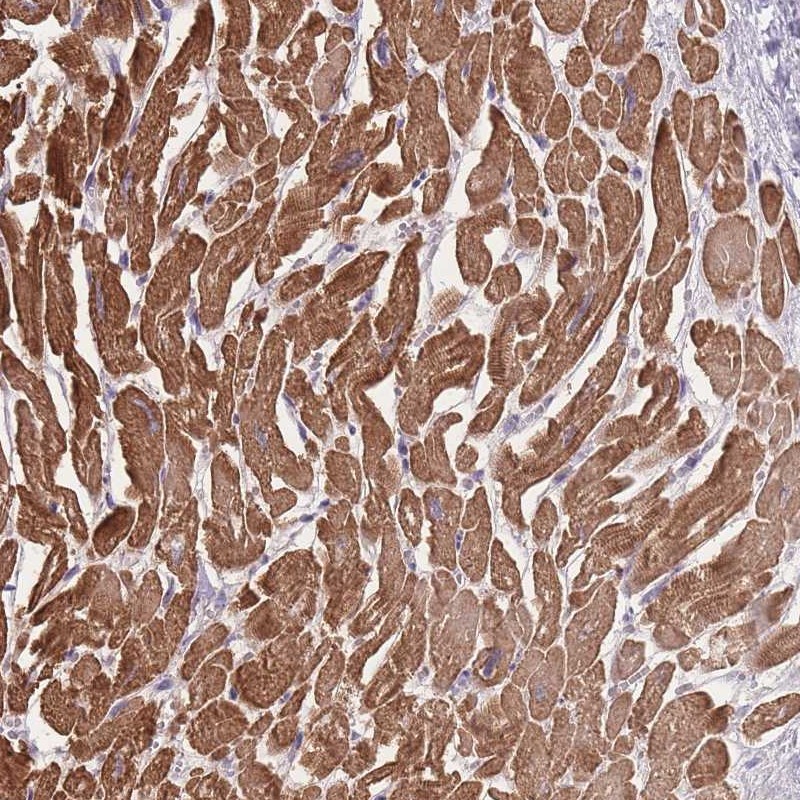

Immunohistochemical staining of human heart muscle shows strong cytoplasmic positivity in myocytes.